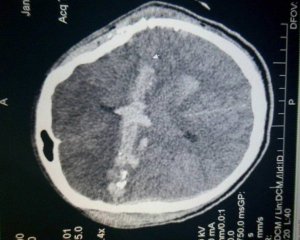

"Іван, 26 років, із Закарпатської області Виноградівського району отримав поранення біля селища Новотроїцьке. Куля увійшла в праву лобову область і вийшла в скроневу зліва. Кома. Штучна вентиляція легень. Військові доправили прямо до реанімаційної зали лікарні Мечникова. Важка нейрохірургічна операція з видаленням мозкового детриту, кісткових уламків. На ранок у Івана з'явилися рухи в кінцівках. З'явилася надія на його порятунок", - пише Риженко.